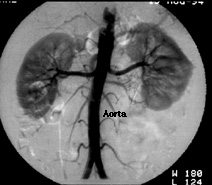

The top image shows an angiogram of the abdominal aorta. Iodinated contrast has been injected into a small catheter placed into the aorta through the femoral artery. The contrast flows into two kidneys. Each kidney is supplied by a single renal artery.

The lower image in this frame shows a 3-D computerized tomographic reconstruction of the same patient. Contrast is injected intravenously and multiple axial images are obtained by a CAT scan machine. These images are then manipulated to show certain regions of interest, in this case, the aorta, renal arteries and the kidneys.